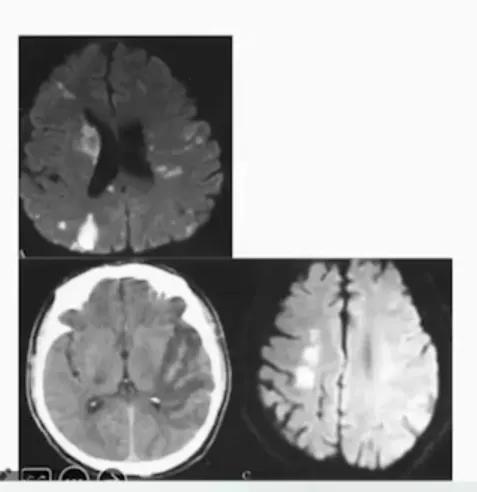

特征

- 范围相对更广

- 交界区分布:内交界区和皮层交界区

- 存在大血管病变时,缺血可呈不对称分布

- 脱水、活动等诱因,补充容量、支架治疗后好转